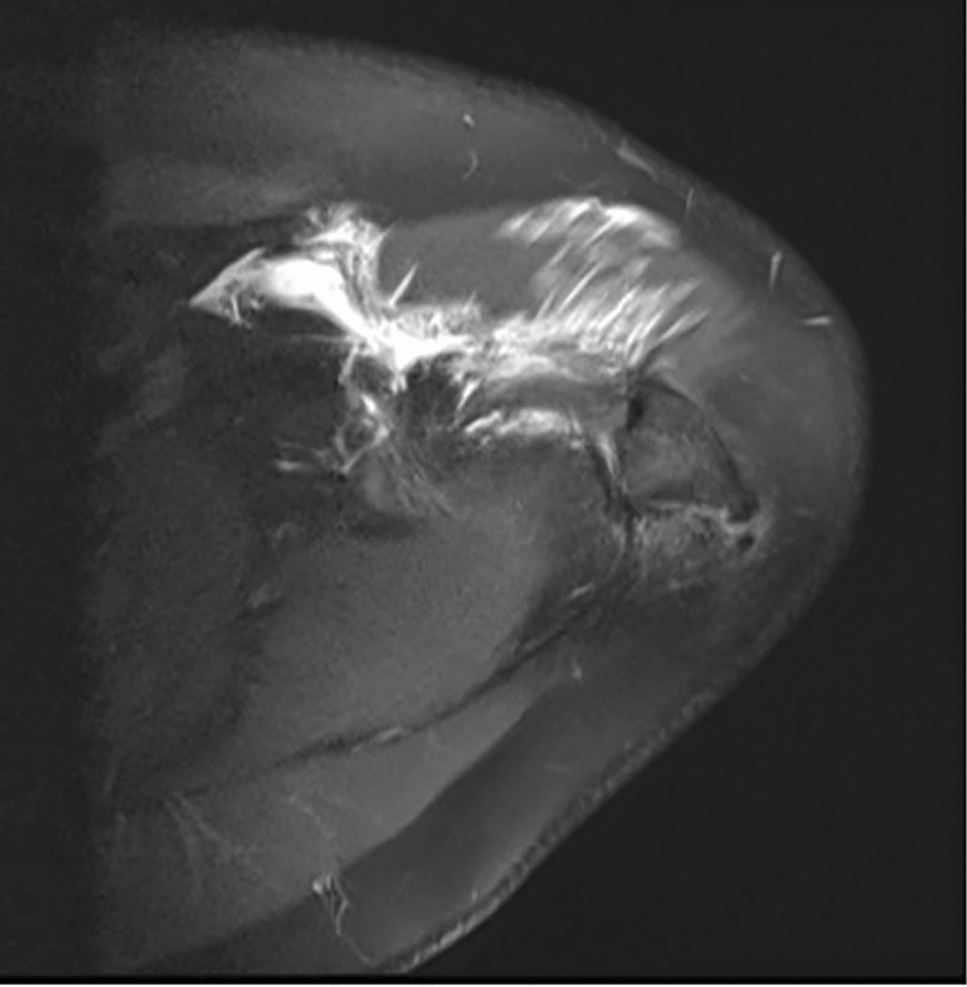

Clinical examination revealed tenderness and pain above the acromial region with a positive impingement sign according to Neer [14]. Active and passive range of motion could be performed without any restrictions. Conventional radiographs and magnetic resonance imaging depicted an os acromiale indicated by a 2.5 cm long fragment in connection with the acromioclavicular joint and additional inflammation of the subacromial bursa (Figs. 1 and 2).

Fig. 2

Magnetic resonance image depicting the os acromiale